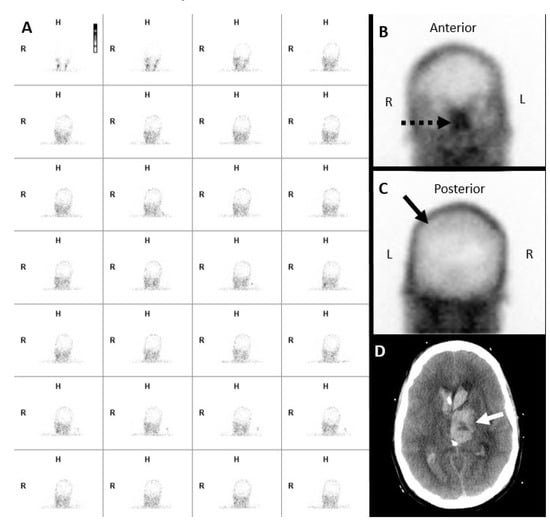

7.1. Nuclear Scintigraphy

- Donohoe, K.J.; Frey, K.A.; Gerbaudo, V.H.; Mariani, G.; Nagel, J.S.; Shulkin, B. Procedure guideline for brain death scintigraphy. J. Nucl. Med. 2003, 44, 846–851. [Google Scholar] [PubMed]

- Donohoe, K.J.; Agrawal, G.; Frey, K.A.; Gerbaudo, V.H.; Mariani, G.; Nagel, J.S.; Shulkin, B.L.; Stabin, M.G.; Stokes, M.K. SNM practice guideline for brain death scintigraphy 2.0. J. Nucl. Med. Technol. 2012, 40, 198–203. [Google Scholar] [CrossRef] [PubMed]

- Al-Shammri, S.; Al-Feeli, M. Confirmation of brain death using brain radionuclide perfusion imaging technique. Med. Princ. Pract. 2004, 13, 267–272. [Google Scholar] [CrossRef] [PubMed]

- Rizvi, T.; Batchala, P.; Mukherjee, S. Brain Death: Diagnosis and Imaging Techniques. Semin. Ultrasound CT MR 2018, 39, 515–529. [Google Scholar] [CrossRef] [PubMed]

- de la Riva, A.; González, F.M.; Llamas-Elvira, J.M.; Latre, J.M.; Jiménez-Heffernan, A.; Vidal, E.; Martínez, M.; Torres, M.; Guerrero, R.; Alvarez, F.; et al. Diagnosis of brain death: Superiority of perfusion studies with 99Tcm-HMPAO over conventional radionuclide cerebral angiography. Br. J. Radiol. 1992, 65, 289–294. [Google Scholar] [CrossRef] [PubMed]

- Wilson, K.; Gordon, L.; Selby, J.B., Sr. The diagnosis of brain death with Tc-99m HMPAO. Clin. Nucl. Med. 1993, 18, 428–434. [Google Scholar] [CrossRef] [PubMed]

- Zuckier, L.S.; Kolano, J. Radionuclide studies in the determination of brain death: Criteria, concepts, and controversies. Semin. Nucl. Med. 2008, 38, 262–273. [Google Scholar] [CrossRef] [PubMed]

- Bertagna, F.; Barozzi, O.; Puta, E.; Lucchini, S.; Paghera, B.; Savelli, G.; Panarotto, B.; Rodella, C.A.; Rebuffoni, L.; Bosio, G.; et al. Residual brain viability, evaluated by (99m)Tc-ECD SPECT, in patients with suspected brain death and with confounding clinical factors. Nucl. Med. Commun. 2009, 30, 815–821. [Google Scholar] [CrossRef] [PubMed]

- Munari, M.; Zucchetta, P.; Carollo, C.; Gallo, F.; De Nardin, M.; Marzola, M.C.; Ferretti, S.; Facco, E. Confirmatory tests in the diagnosis of brain death: Comparison between SPECT and contrast angiography. Crit. Care Med. 2005, 33, 2068–2073. [Google Scholar] [CrossRef] [PubMed]

- Bonetti, M.G.; Ciritella, P.; Valle, G.; Perrone, E. 99mTc HM-PAO brain perfusion SPECT in brain death. Neuroradiology 1995, 37, 365–369. [Google Scholar] [CrossRef] [PubMed]

- Appelt, E.A.; Song, W.S.; Phillips, W.T.; Metter, D.F.; Salman, U.A.; Blumhardt, R. The “hot nose” sign on brain death nuclear scintigraphy: Where does the flow really go? Clin. Nucl. Med. 2008, 33, 55–57. [Google Scholar] [CrossRef] [PubMed]

- Mrhac, L.; Zakko, S.; Parikh, Y. Brain death: The evaluation of semi-quantitative parameters and other signs in HMPAO scintigraphy. Nucl. Med. Commun. 1995, 16, 1016–1020. [Google Scholar] [CrossRef] [PubMed]

- Lee, V.W.; Hauck, R.M.; Morrison, M.C.; Peng, T.T.; Fischer, E.; Carter, A. Scintigraphic evaluation of brain death: Significance of sagittal sinus visualization. J. Nucl. Med. 1987, 28, 1279–1283. [Google Scholar] [PubMed]